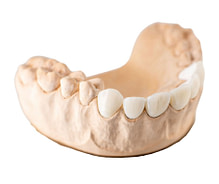

Crowns and Bridges

Inlays and Onlays

Digital VS Analog

Digital dentistry helps you streamline workflows, reduce chair time, and provide patients with an unparalleled experience.

Digital impression systems eliminate the mess, discomfort, and inaccuracies of traditional putty impressions, allowing for precise digital models.

CAD/CAM same-day crowns cut out the need for multiple appointments and temporary restorations.